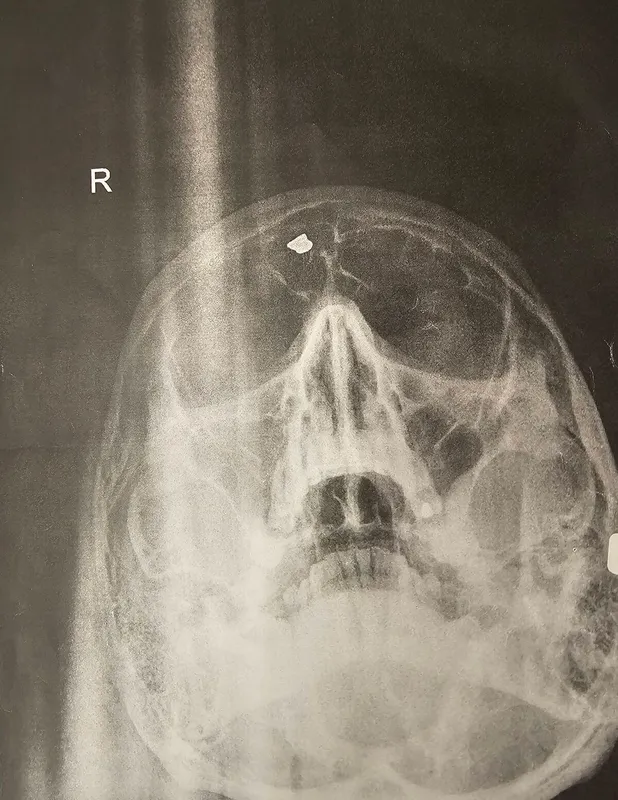

Gabriella egyik betege veseproblémákra panaszkodott, ezért gócpontkutatásra elküldte őt, hogy nyomára bukkanjanak, mégis mi okozhatja azokat. A Heves vármegyei férfi jót derült az orvosával, amikor kézhez vették a koponyaröntgen eredményét: a férfi homloküregében egy fehér folt látszott – egy sörétes golyót rejtett a koponyája!

„Az egész teljesen véletlenül derült ki. Nem is tudta, hogy ott van a fejében az a golyó” – árulta el a Ripostnak Gabriella.

Mutatjuk a röntgen fotót!

„A fül-orr gégészeten vizsgálták meg, és a beteg külön elhozta, hogy látnom kell. Egy olyan kuriózum. Negyven éve ott van a fejében egy fémdarab, amiről nem tudott. Sokat utazik ez a betegem, jó hogy nem jelzett be neki a fémdetektor. De sajnos ez lenne a legkisebb gond. Nem látszik a felvételen, hogy mennyire mélyen van sörétes golyó – az agyszövetbe vagy a csontba fúródva. Akár veszélyes is lehet, ha mondjuk egy MRI-re elmegy. Ahogy az sem tiszta, hogy ez mennyire kockázatos egy olyan vizsgálat során. Ezért most amíg ez ki nem derül, a férfi nem megy ilyen vizsgálatra” – árulta el a háziorvos.

A röntgenfotót az ország háziorvosa a közösségi oldalán is megosztotta, kiemelve: szerencse, hogy a betegének nem lett komolyabb baja a lövés miatt. Bejegyzésére rengetegen megírták, hogy nekik milyen veszélyes csíntevésük volt.